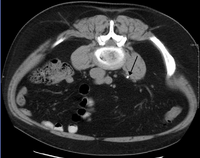

Imaging studies

Calcium-containing stones are relatively radiodense, and they can often be detected by a traditional radiograph of the abdomen that includes the kidneys, ureters, and bladder (KUB film).[28] Some 60% of all renal stones are radiopaque.[29][30] In general, calcium phosphate stones have the greatest density, followed by calcium oxalate and magnesium ammonium phosphate stones. Cystine calculi are only faintly radiodense, while uric acid stones are usually entirely radiolucent.[31]

Where available, a noncontrast helical CT scan with 5 millimeters (0.20 in) sections is the diagnostic modality of choice in the radiographic evaluation of suspected nephrolithiasis.[3][26][29][32][33] All stones are detectable on CT scans except very rare stones composed of certain drug residues in the urine,[28] such as from indinavir.

Ultrasound imaging of the kidneys can sometimes be useful, as it gives details about the presence of hydronephrosis, suggesting the stone is blocking the outflow of urine.[28] Radiolucent stones, which do not appear on KUB, may show up on ultrasound imaging studies. Other advantages of renal ultrasonography include its low cost and absence of radiation exposure. Ultrasound imaging is useful for detecting stones in situations where X-rays or CT scans are discouraged, such as in children or pregnant women.[34] Despite these advantages, renal ultrasonography is not currently considered a substitute for noncontrast helical CT scan in the initial diagnostic evaluation of urolithiasis.[32] The main reason for this is that compared with CT, renal ultrasonography more often fails to detect small stones (especially ureteral stones), as well as other serious disorders that could be causing the symptoms.[1]